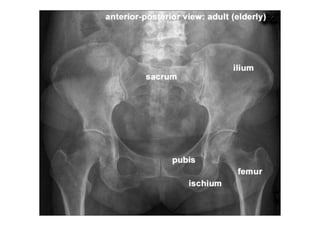

Radiologia Convencional ou Radiografia Simples ou

Raio X Simples Musculoesqauelético

• Radiografia da coluna cervical

• Radiografia da coluna torácica

• Radiografia da coluna lombar

• Radiografia de tórax

• Radiografia do ombro

• Radiografia do cotovelo

• Radiografia do antebraço

• Radiografia do punho

• Radiografia da mão

• Radiografia do abdômen

• Radiografia da bacia (pelve)

• Radiografia do quadril

Fonte: info-radiologie.ch

• Radiografia do joelho

• Radiografia do tornozelo

• Radiografia do pé